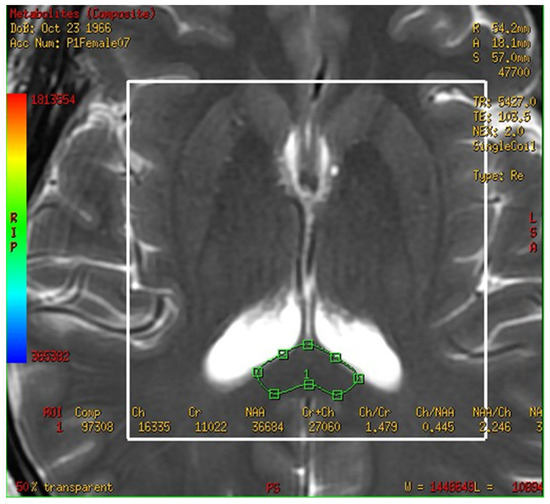

Figure 2.

Magnetic resonance spectroscopy with three-dimensional chemical shift images in the chosen location of the bilateral corpus callosum (green markup). The signal intensities of metabolites were measured and recorded.